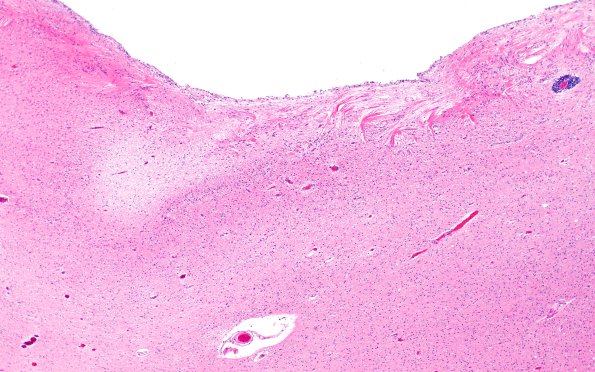

Washington University Experience | BASIC PROCESSES | Astrocytes & Astrocytosis | Astrocytosis | 11A5 Cerebral Palsy (Case 23) H&E 4X

A second site in the periventricular region of this patient showing prominent astrocytosis and wheat sheaving.